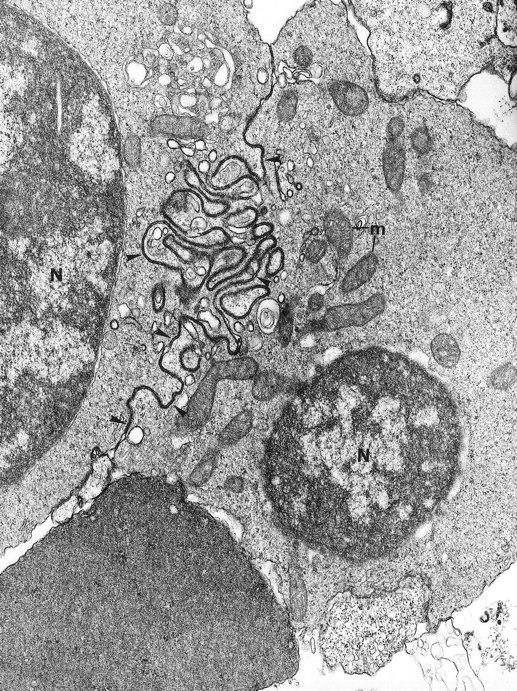

Electron microscopy confirmed the diagnosis of erythroblastic synartesis in the 3 patients. Plasma membranes of adjacent erythroblasts were joined by closely interdigitating processes (Fig2). Cytochemical demonstration of the peroxidatic activity of hemoglobin (not shown) allowed identification of maturation stages of the erythroblasts, because its level of intensity relates to the hemoglobin content of each cell. This technique showed that erythroblasts of the same maturation stage, as well as those of different maturation stages, were linked. Ribosomes were absent at sites of linkage via interdigitating process, corresponding with the nonbasophilic areas observed by light microscopy (Fig3a). At the junction sites, coated pits and rhopheocytosis vesicles were absent, probably because a macrophage expansion would find it impossible to penetrate this zone of tightly linked plasma membrane. Ferritin granules were never observed within these junctions. Junctions between erythroblasts had a characteristic morphology: resembling gap junctions, they were formed by 2 closely placed membranes joined by periodical structures every 150 Å, giving rise to a zipper-like appearance (Fig 3b). Isolated normoblasts often displayed picnotic nuclei and/or binuclearity. The 2 external leaflets of the plasma membrane of adjacent erythroblasts were separated by a constant space of 145 Å in patient 1, and 180 Å in patients 2 and 3.

Fig. 2.

The electron microscopic aspect of the bone marrow erythroblasts from patient 1: Cells are joined by interdigitating processes of the plasma membrane (arrowheads). They delineate areas of cytoplasm which are deprived of ribosomes (N, nucleus; m, mitochondria). Original magnification: ×21,000.

Close modal